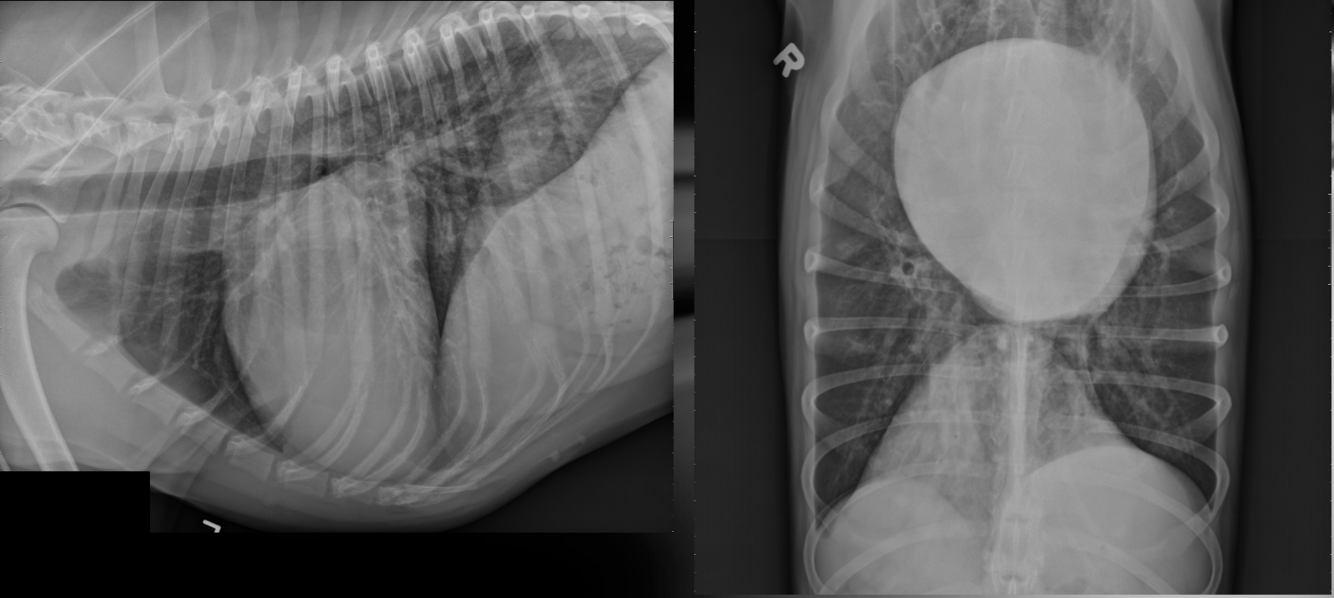

Q

What is shown in these images?

A

patent ductus arteriosus

-LVE and LAE

-normal to large pulmonary vessels

-triple bump sign

What are the radiographic findings in patent ductus arteriosis?

*LVE and LAE due to volume overload

*normal to large pulmonary vessels

*possible left heart failure

*triple bump sign:

-aneurysmal dilatation of proximal descending aorta

-MPA segment enlargement

-enlargement of left auricle